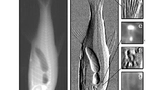

Bild 5

Bild 5. Durchleuchtetes Rattenherz: links konventionelles Absorptionsbild, Mitte differenzielles DPC-Bild, rechts integriertes DPC-Bild.

Welche Qualität damit gewonnene Bilder haben, ist in Bild 5 zu sehen. Es handelt sich um ein Rattenherz, einmal im konventionellen Absorptionsbild aufgenommen (links), dann im Phasendifferenzbild, das die Kanten hervorhebt (Mitte) und schließlich als integriertes Bild (rechts), das wiederum die Dichte wiedergibt. Bei dem in Bild 6 gezeigten Fisch sind drei Teilbereiche herausvergrößert, jeweils einmal mit konventioneller Technik und einmal mit DPC aufgenommen.